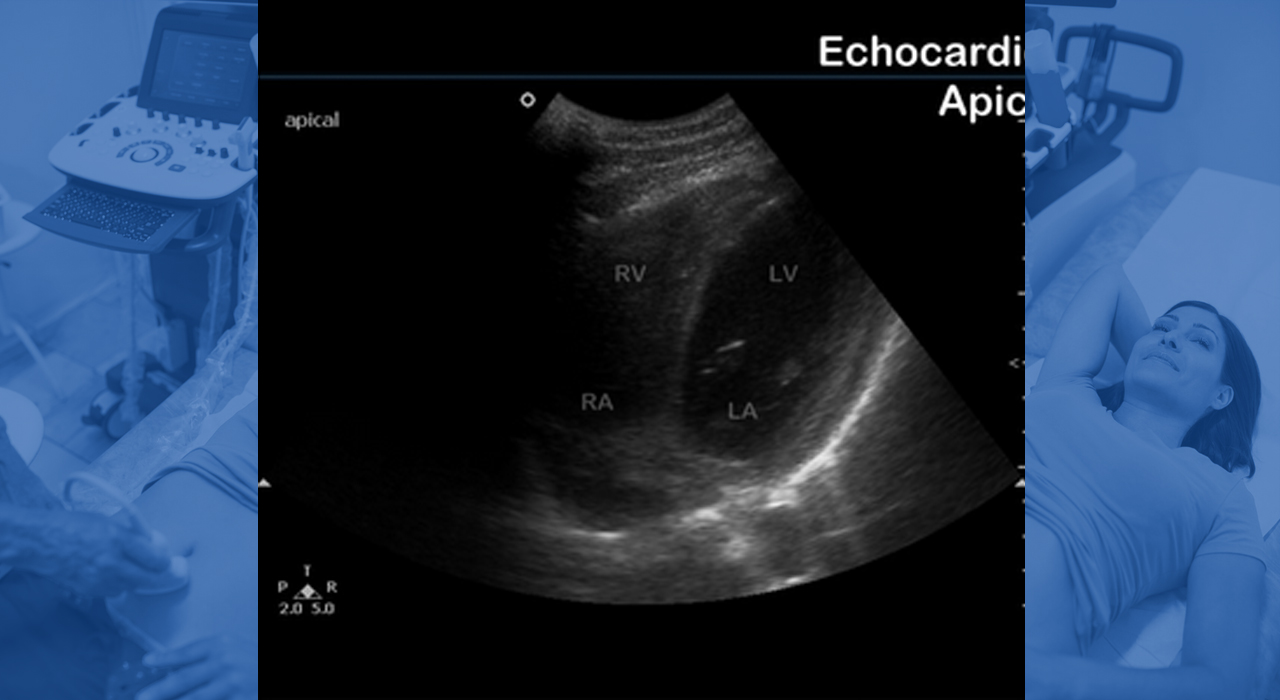

- USOS MÚLTIPLES: puede usarse durante la resuscitación (RCP), diagnóstica, para guiar procedimentos y monitoreo del paciente.

- ÁREAS Y PROTOCOLOS- RCP (Rush), pulmonar, cardiaco, vasos sanguíneos, abdominal, emergencias, trombosis venosa, tejidos blandos y tiroides.